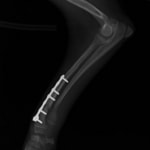

症例:交通事故による椎体脱臼

柴犬:9歳、避妊雌

交通事故直後、胸腰部に激しい疼痛、両後肢に完全麻痺を認め、シェフシェリントン徴候を呈していました。レントゲン検査において、第11-12胸椎間の脱臼が認められました。

脊髄の減圧、脊柱管の再構築・安定化を目的に、片側椎弓切除術およびMatrixMANDIBLE Plateによる椎体固定を実施しました。

隣接椎体を架橋するようにプレートを設置しました。

術後レントゲン写真